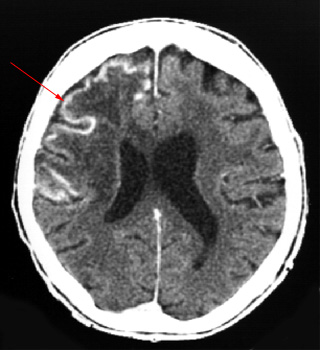

Head CT > Stroke > Enhancement in Infarctions

Enhancement in Infarctions

Ninety percent of infarcts enhance on CT examinations with intravenous contrast at 1 week after the infarct. Approximately 35% enhance by 3 days. Faint enhancement begins near the pial surface or near the infarct margins. The enhancement is initially smaller than the area of infarction. It subsequently becomes gyriform. Enhancement is due to breakdown of the blood brain barrier, neovascularity, and reperfusion of damaged brain tissue.